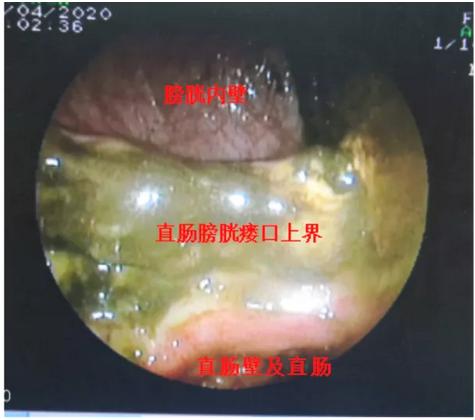

次日,胡石甫医生为该患者进行普通肠镜检查发现其直肠肿瘤全腔生长,结肠镜无法通过评估肿瘤近端状况,遂后胡石甫医生考虑到我院内镜室装备,利用超细内镜再次 进镜 尝试,终于通过了肿瘤上方,但由于患者长期直肠梗阻造成肿瘤上方大量粪便蓄积,局部无法判断内瘘部位及瘘口大小,最终胡石甫医生耐心地通过超细内镜活检孔道利用大量盐水进行内镜下肠道反复盥洗,将近端肠内粪便冲洗大半,为患者再次内镜检查及减少粪便进入膀胱内打下基础。治疗结束后,患者自觉膀胱刺激症状及肠梗阻情况有明显改善。

接下来通过近5天的抗炎+肠外营养+膀胱持续冲洗治疗后,患者机体较前明显改善。胡石甫医生再次尝试超细内镜下明确瘘口状态,通过反复盐水冲洗梗阻近端后,终于精准测量出肿瘤病变长度,同时完整显露膀胱后壁瘘口全貌,“直肠肿瘤全腔狭窄病变长径6cm,直肠膀胱瘘口大小约4cm*3cm,近1/3圈直肠前壁缺损,瘘口周围肠壁因为放疗呈大范围的糜烂充血水肿改变”。